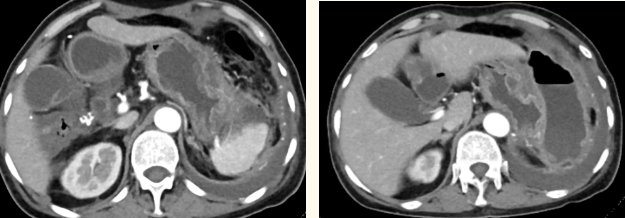

一籌莫展的她終于在病友的介紹下,來到西安國際醫(yī)學中心醫(yī)院找到蔡磊主任。經(jīng)過詢問病史,查體等,蔡磊主任建議口服索坦治療。3個月后,李阿姨復查CT提示胃間質(zhì)瘤較前明顯縮小,大小約10.4cm?6cm。但仍存在消化道出血,營養(yǎng)狀況差,全身無力,骨髓抑制。蔡磊主任隨即將患者收治入院。